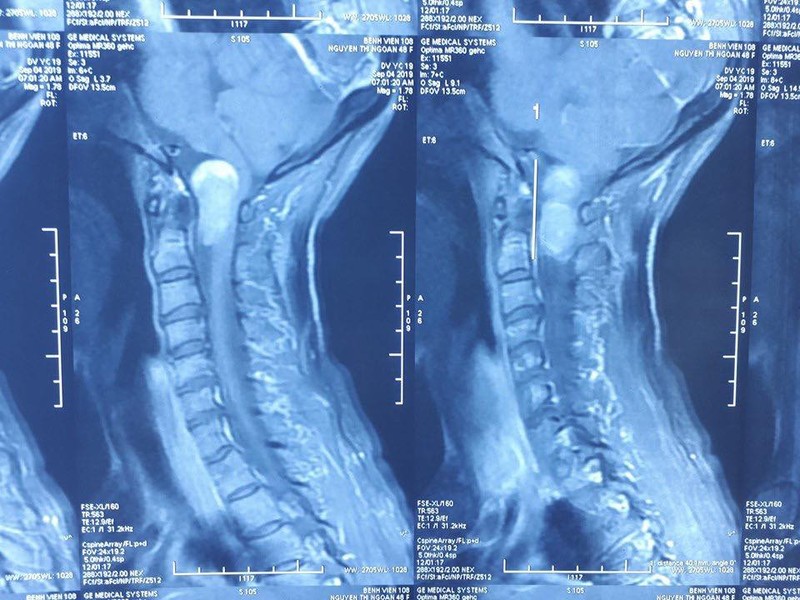

Kết quả chụp X-quang chỉ ra bà N. có khối u rễ thần kinh vùng chẩm cổ, khối u chèn ép tủy sống và hành tủy. Khối u này đã phát triển ống sống lan tỏa lên sọ não, vì vậy các bác sĩ chỉ định bà N. phải mổ ngay.

Ảnh chụp X-quang vị trí khối u của bà N.

Bên cạnh đó, khối u nằm ở vị trí vùng chẩm cổ - nơi có liên quan đến hô hấp, tuần hoàn - nên việc phẫu thuật rất khó khăn. Các bác sĩ phải khéo léo để loại bỏ hoàn toàn khối u, đồng thời đảm bảo không xảy ra biến chứng suy hô hấp cho bệnh nhân.

Nỗ lực của các bác sĩ đã thành công, khi loại bỏ hoàn toàn khối u ở vùng chẩm cổ có kích thức 3x2cm, giúp bà N. không còn phải chịu đựng ảnh hưởng xấu của khối u quái ác.